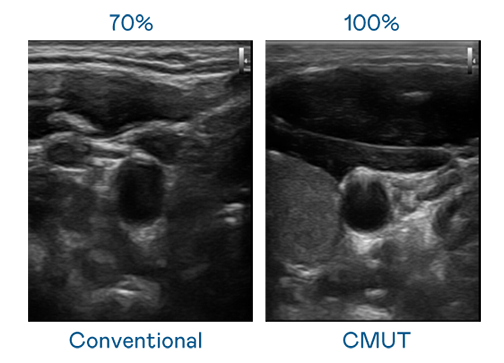

CMUT 技术是一种用电容式微机电元件来产生超音波讯号的技术。与传统 PZT 压电式技术相比,CMUT 频宽增加 30%,更宽频的超音波讯号让影像解析度大幅提升,是实现高影像品质医疗超音波扫描、促进精准医疗发展的关键技术。

超音波影像的解析度高低,首先取决于探头能发出的讯号频宽。4556银河国际 CMUT 可提供高清晰的超音波讯号,提供高频宽、高灵敏度、影像纹理细节更高的超音波影像,协助医护人员缩短影像判读时间及利用精准的医疗影像进行诊断。